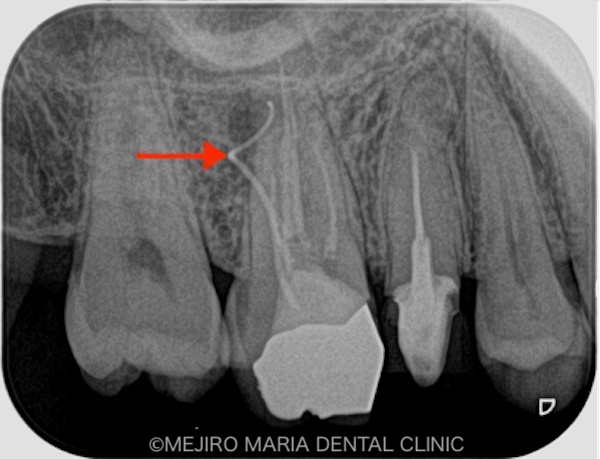

右上の歯を確認したとろ、当該部位にはフィステル(瘻孔)が確認でき、フィステルより造影してみると、右上6番の歯の根尖部付近から、排膿されていることがわかりました(写真の赤矢印)。フィステル以外に痛みなどの所見は見当たらないものの、「根尖性歯周炎」と診断し、治療を開始しました。